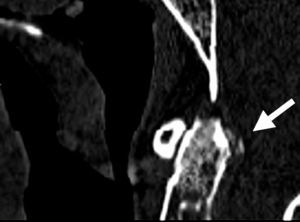

Axial skeleton affection due to chondrocalcinosis has been associated to calcium deposits in the intervertebral disc, the yellow ligament, the fact joints and even the sacroiliac joints. Calcification of the transverse ligament of the atlas (Figs. 1–3) is an infrequent manifestation and has been denominated the Crown Dens syndrome. It mostly constitutes an asymptomatic clinical picture but may be associated with episodes of acute cervical pain, stiffness and fever, with the added diagnostic difficulties of these cases.

We present the case of an 82-year-old woman who consulted us due to intense cervical pain which responded poorly to analgesics. She had a history of atrial fibrillation undergoing anticoagulation therapy, spondyloarthritis and radiologic chondrocalcinosis of the knees. Physical examination revealed spontaneous pain on the cervical spine, radiating to the occipital and mastoid regions, with stiffness and movement limitations due to pain, with no neurologic manifestations.

The Crowned Dens syndrome was described initially in 1985 by Bouvet et al.1,2 Diagnosis is based on the association of a compatible clinical picture and imaging findings, mainly calcium deposits in atlas-axis joint ligaments, visible on CT.3,4